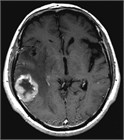

1. JCOG0504試験によって、摘出術後に全脳照射を行う必要はなく、摘出後残存がない場合は経過観察、残存がある場合は定位放射線照射を行うことが標準治療となった。またBrown/Mahajanの臨床試験によると、摘出後に残存がなくとも定位放射線照射を行うことにより、有意に摘出腔の局所制御率が高くなることが報告された(推奨度1)